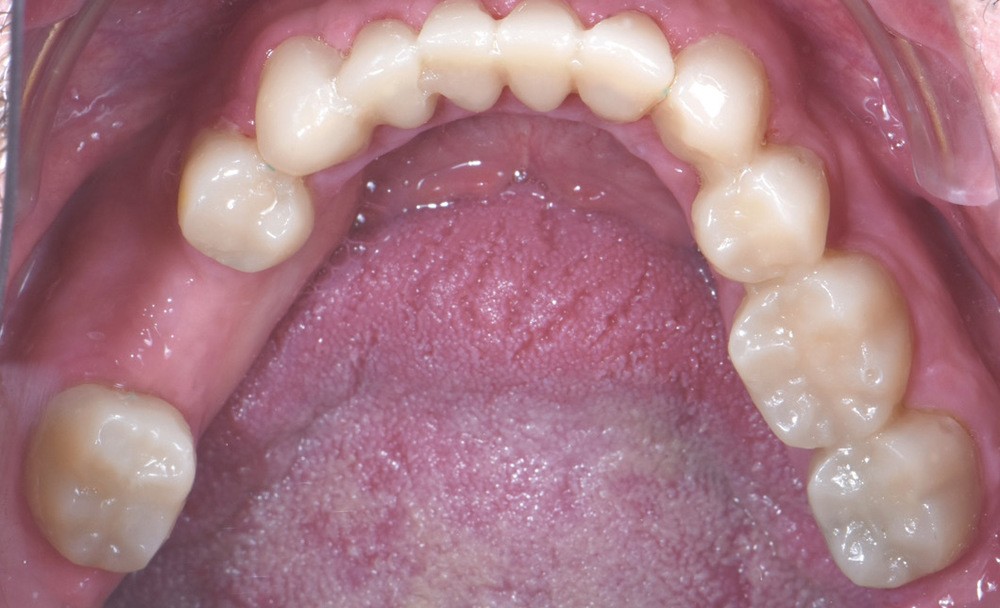

Au vu du contexte para-fonctionnel et de l’étendue de la perte tissulaire, des coiffes périphériques minimalement invasives ont été choisies afin de restaurer l’esthétique et la fonction. Actuellement, aucun consensus n’est fait sur le choix du matériau d’infrastructure à privilégier. Les matériaux hybrides usinables présentent des propriétés mécaniques, physiques et biologiques intéressantes en contexte d’usure sévère (e.g., module d’élasticité, résistance à la propagation de fêlures, facilité de réintervention). Une réhabilitation globale avec remontée de dimension verticale d’occlusion (DVO) par l’intermédiaire de coiffes composites renforcés en nano-céramiques est décrite.